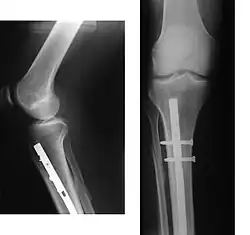

- Osteosynthesa znamená operační řešení, při kterém je kost zpevněna nejčastěji kovovým materiálem, kterým je nějaký druh nerezové oceli, titanuové slitiny, kompozitu atp., který se po čase buď vyjme, nebo někdy i ponechá. Existuje řada metod (vnitřní fixace, zevní fixace), od jednoduchých cerkláží ocelovými dráty, přes šrouby doplněné dlahami až po nejrůznější systémy hřebování s předvrtáváním nebo bez něj (hřeb znamená navlečení nejčastěji dlouhé a duté kosti na pevný a dlouhý ocelový profil, který je na konci zafixován šrouby. Po čase se šrouby na jednom zpravidla distálním (vzdáleném) konci vyjmou, čemuž se říká dynamizace).

- Vnitřní fixace je ,v souladu s předchozím textem, osteosyntéza pomocí hřebů, dlah, šroubů, svazků drátů. Implantát je aplikován uvnitř těla a vyjmout lze jen operativně a nejčastěji se v těle ponechá trvale.